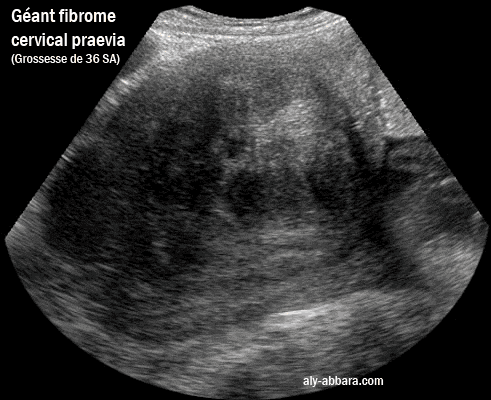

Géant fibrome cervical praevia chez femme enceinte, une primipare à 36 SA